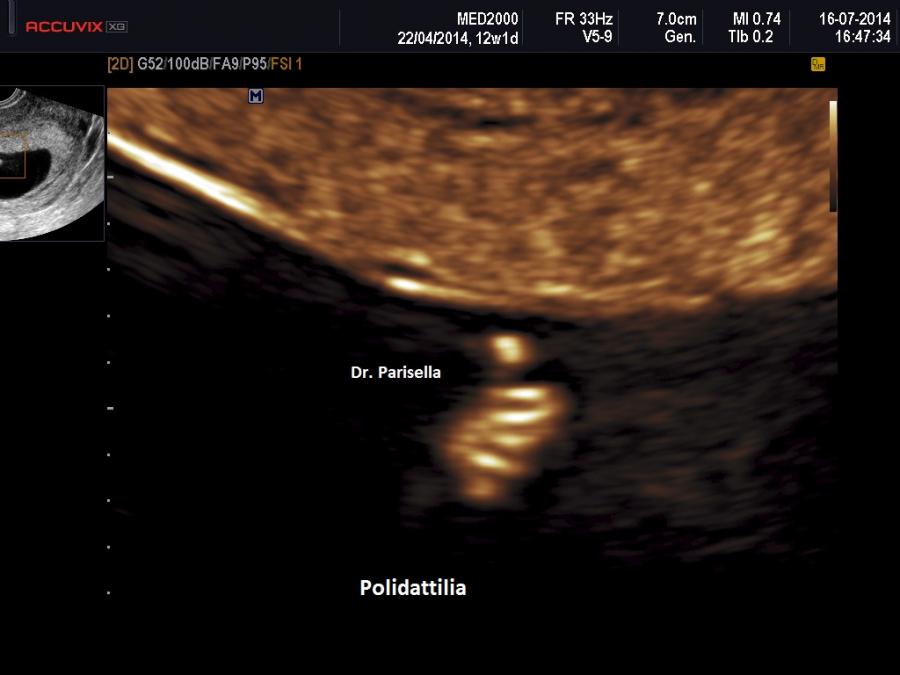

Il sospetto in diagnosi prenatale  ecografica si basa sul riscontro delle seguenti anomalie fetali:

4. polidattilia